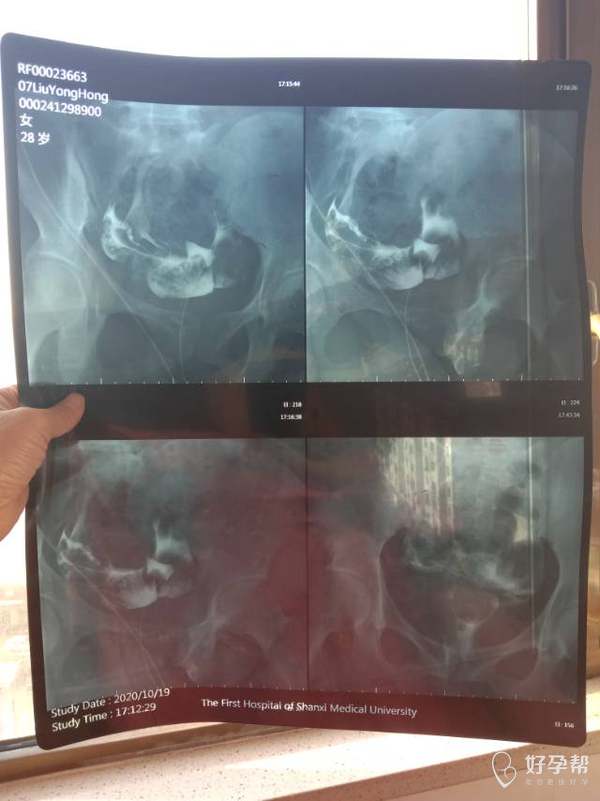

这种必须做手术么还是取了胚胎不是非要做

段雅贞

这个手术不是非得要马上做,需要根据你的年龄、生育计划等来综合评估并权衡利弊后再决定是否需要手术以及什么时候做。如果是做试管通常为了避免输卵管积液及炎症因子逆流至宫腔影响胚胎着床等,会行输卵管结扎等手术,这个手术通常在移植前完成